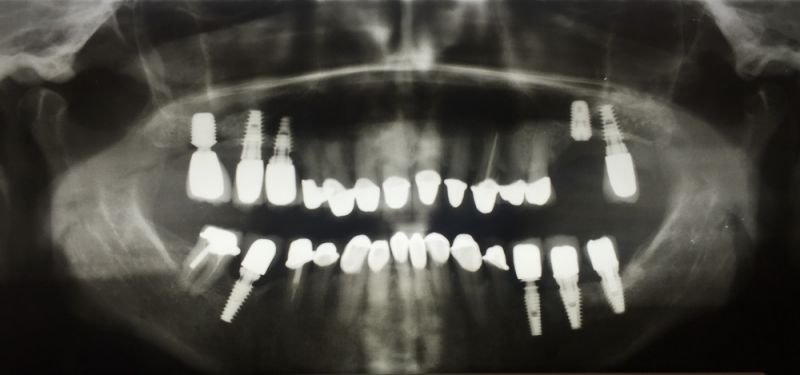

Auf dem osseointegrierten Implantat 17 wurde heute eine neue Krone festgesetzt.

Im Anschluss daran wurde in regio 26 unter Anwendung eines bone splitting ein neues Implantat 26 inseriert.

Die Erstversorgung der Patientin resultierte aus dem Jahr 2007/8